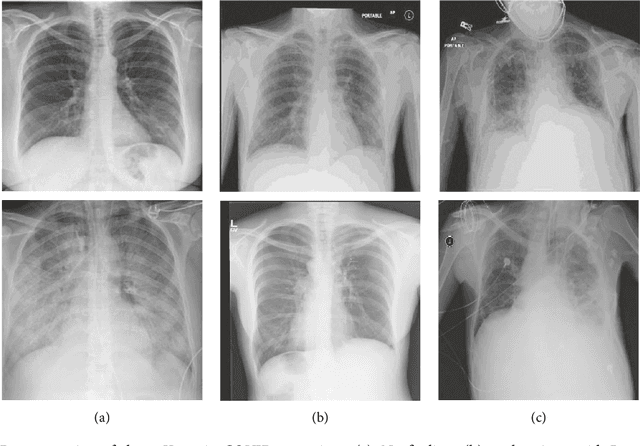

Abstract:The COVID-19 disease was first discovered in Wuhan, China, and spread quickly worldwide. After the COVID-19 pandemic, many researchers have begun to identify a way to diagnose the COVID-19 using chest X-ray images. The early diagnosis of this disease can significantly impact the treatment process. In this article, we propose a new technique that is faster and more accurate than the other methods reported in the literature. The proposed method uses a combination of DenseNet169 and MobileNet Deep Neural Networks to extract the features of the patient's X-ray images. Using the univariate feature selection algorithm, we refined the features for the most important ones. Then we applied the selected features as input to the LightGBM (Light Gradient Boosting Machine) algorithm for classification. To assess the effectiveness of the proposed method, the ChestX-ray8 dataset, which includes 1125 X-ray images of the patient's chest, was used. The proposed method achieved 98.54% and 91.11% accuracies in the two-class (COVID-19, Healthy) and multi-class (COVID-19, Healthy, Pneumonia) classification problems, respectively. It is worth mentioning that we have used Gradient-weighted Class Activation Mapping (Grad-CAM) for further analysis.

Abstract:The Coronavirus was detected in Wuhan, China in late 2019 and then led to a pandemic with a rapid worldwide outbreak. The number of infected people has been swiftly increasing since then. Therefore, in this study, an attempt was made to propose a new and efficient method for automatic diagnosis of Corona disease from X-ray images using Deep Neural Networks (DNNs). In the proposed method, the DensNet169 was used to extract the features of the patients' Chest X-Ray (CXR) images. The extracted features were given to a feature selection algorithm (i.e., ANOVA) to select a number of them. Finally, the selected features were classified by LightGBM algorithm. The proposed approach was evaluated on the ChestX-ray8 dataset and reached 99.20% and 94.22% accuracies in the two-class (i.e., COVID-19 and No-findings) and multi-class (i.e., COVID-19, Pneumonia, and No-findings) classification problems, respectively.

Abstract:The new coronavirus (known as COVID-19) was first identified in Wuhan and quickly spread worldwide, wreaking havoc on the economy and people's everyday lives. Fever, cough, sore throat, headache, exhaustion, muscular aches, and difficulty breathing are all typical symptoms of COVID-19. A reliable detection technique is needed to identify affected individuals and care for them in the early stages of COVID-19 and reduce the virus's transmission. The most accessible method for COVID-19 identification is RT-PCR; however, due to its time commitment and false-negative results, alternative options must be sought. Indeed, compared to RT-PCR, chest CT scans and chest X-ray images provide superior results. Because of the scarcity and high cost of CT scan equipment, X-ray images are preferable for screening. In this paper, a pre-trained network, DenseNet169, was employed to extract features from X-ray images. Features were chosen by a feature selection method (ANOVA) to reduce computations and time complexity while overcoming the curse of dimensionality to improve predictive accuracy. Finally, selected features were classified by XGBoost. The ChestX-ray8 dataset, which was employed to train and evaluate the proposed method. This method reached 98.72% accuracy for two-class classification (COVID-19, healthy) and 92% accuracy for three-class classification (COVID-19, healthy, pneumonia).

Abstract:In late 2019 and after COVID-19 pandemic in the world, many researchers and scholars have tried to provide methods for detection of COVID-19 cases. Accordingly, this study focused on identifying COVID-19 cases from chest X-ray images. In this paper, a novel approach to diagnosing coronavirus disease from X-ray images was proposed. In the proposed method, DenseNet169 deep neural network was used to extract the features of X-ray images taken from the patients' chest and the extracted features were then given as input to the Extreme Gradient Boosting (XGBoost) algorithm so that it could perform the classification task. Evaluation of the proposed approach and its comparison with the methods presented in recent years revealed that the proposed method was more accurate and faster than the existing ones and had an acceptable performance in detection of COVID-19 cases from X-ray images.